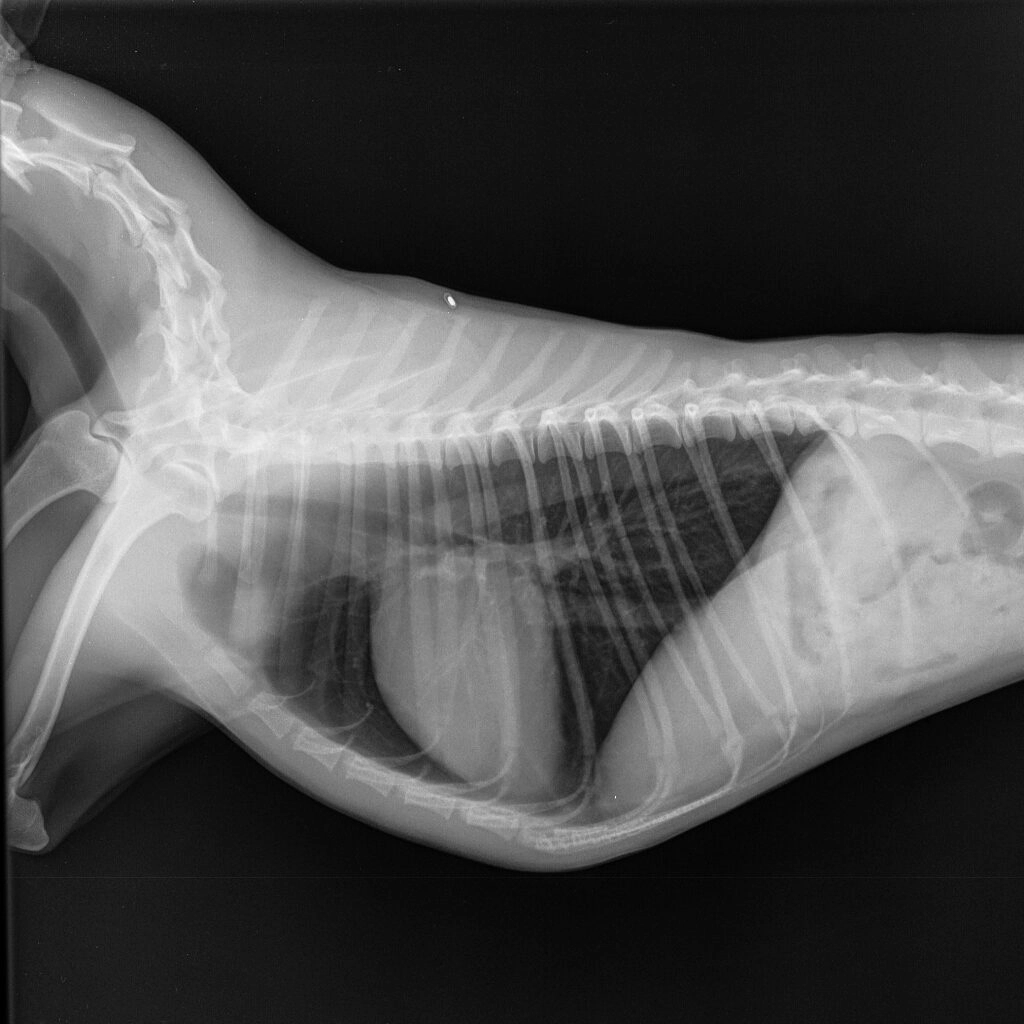

Отделение рентгенодиагностики оборудовано современной системой получения рентгеновских снимков и позволяет получать изображения грудной клетки в высоком разрешении (сердце, сосуды, легкие, трахея и др.). Это позволяет заметить даже незначительные изменения размеров сердца, новообразования маленьких размеров, верно оценить структуру тканей.